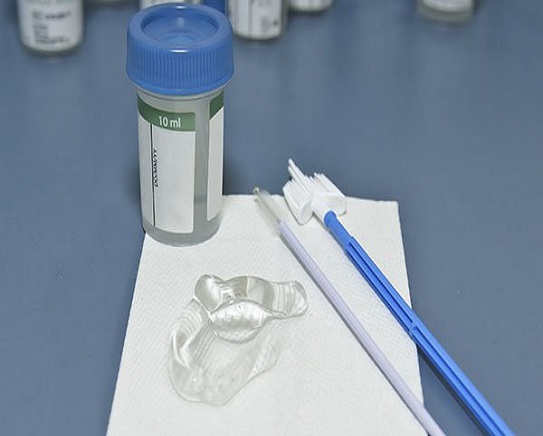

Liquid Based Cytology

Cervical cancer is most prevalent cancer in Indian women which is a preventive cancer. Routine screening and reliable pap smear results are very important factors for timely diagnosis of cervical cancer.

We have in house processing unit of Liquid Based cytology for Cervical Pap smears which is very useful test in cervical cancer detection.

Liquid Based Cytology

Cervical cancer is most prevalent cancer in Indian women which is a preventive cancer. Routine screening and reliable pap smear results are very important factors for timely diagnosis of cervical cancer.

We have in house processing unit of Liquid Based cytology for Cervical Pap smears which is very useful test in cervical cancer detection.